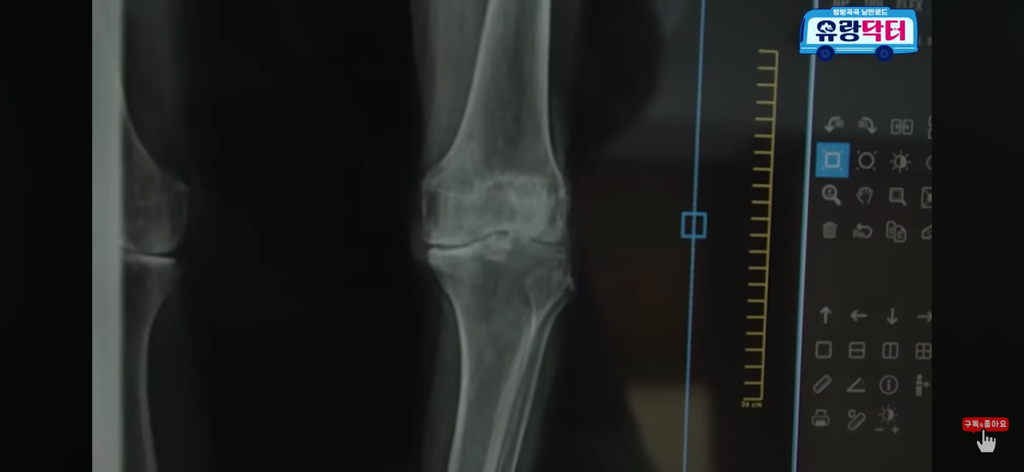

20년 넘게 뼈가 굳어서 죽었다고 말씀하심

+ 찾아보니까 FIMS 치료라고 하고

1번으로는 효과 기대하기 힘들고

3번은 받으면 그래도 점차 나아지긴 한대

근데 3번 정도 받는다고 완전히 펴지는 건 아니고

90도가 60도 되고 60도가 30도 되고

그렇게 점차 효과를 보는 치료인 것 같음

한 번만으론 절대 안 됨!